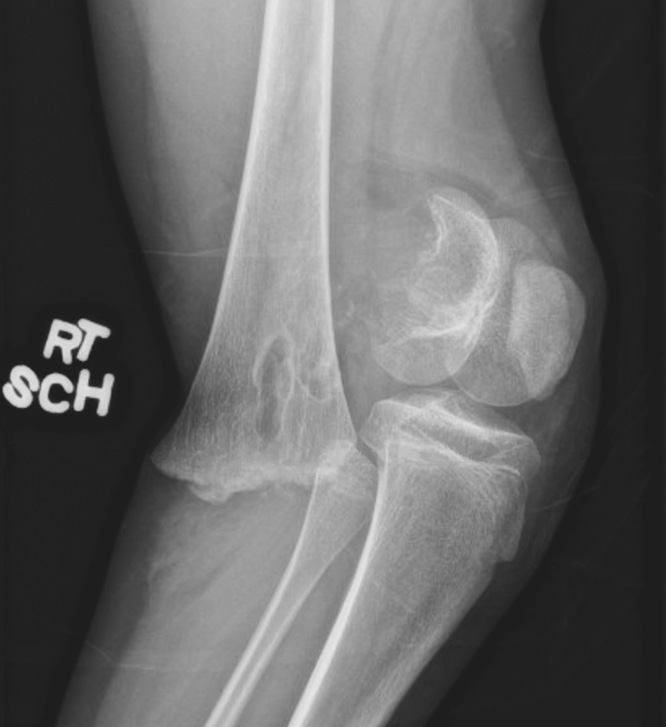

Рентген показал перелом дистального отдела правой бедренной кости с сильным смещением и повреждением зоны роста (рис. 2). При осмотре была выявлена колотая рана в задней части бедра, выстояние надколенника, рекурвация конечности и ее вынужденное сгибание в коленном суставе. Рот пациентки был относительно маленьким, но не было отмечено аномалий нёба или сколиоза. Периферическая чувствительность и разгибательная функция большого пальца стопы нарушены не были. Пульс на тыльной артерии стопы с двух сторон ощущался пальпаторно на 3+ и был подтвержден допплерографически. Лодыжечно-плечевой индекс правой и левой нижних конечностей составил 1,2 и 1,1 соответственно. Родители пациентки были уведомлены о возможном нарушении роста. Вакцинация против столбняка была проведена своевременно. Перед операцией был введен 1 г цефазолина внутривенно.

Рис. 2. Рентгенограмма правого коленного сустава в боковой проекции, показывающая перелом дистального отдела бедренной кости Салтер – Харриса 2-го типа со смещением